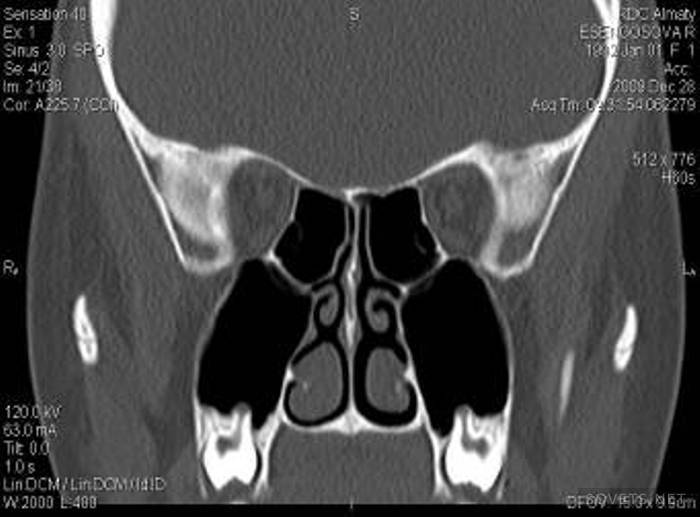

O SKT de olhos, fragmentos de face e seios é amplamente praticado. O dispositivo encontra violações na estrutura desses órgãos e corpos estranhos que penetraram neles.